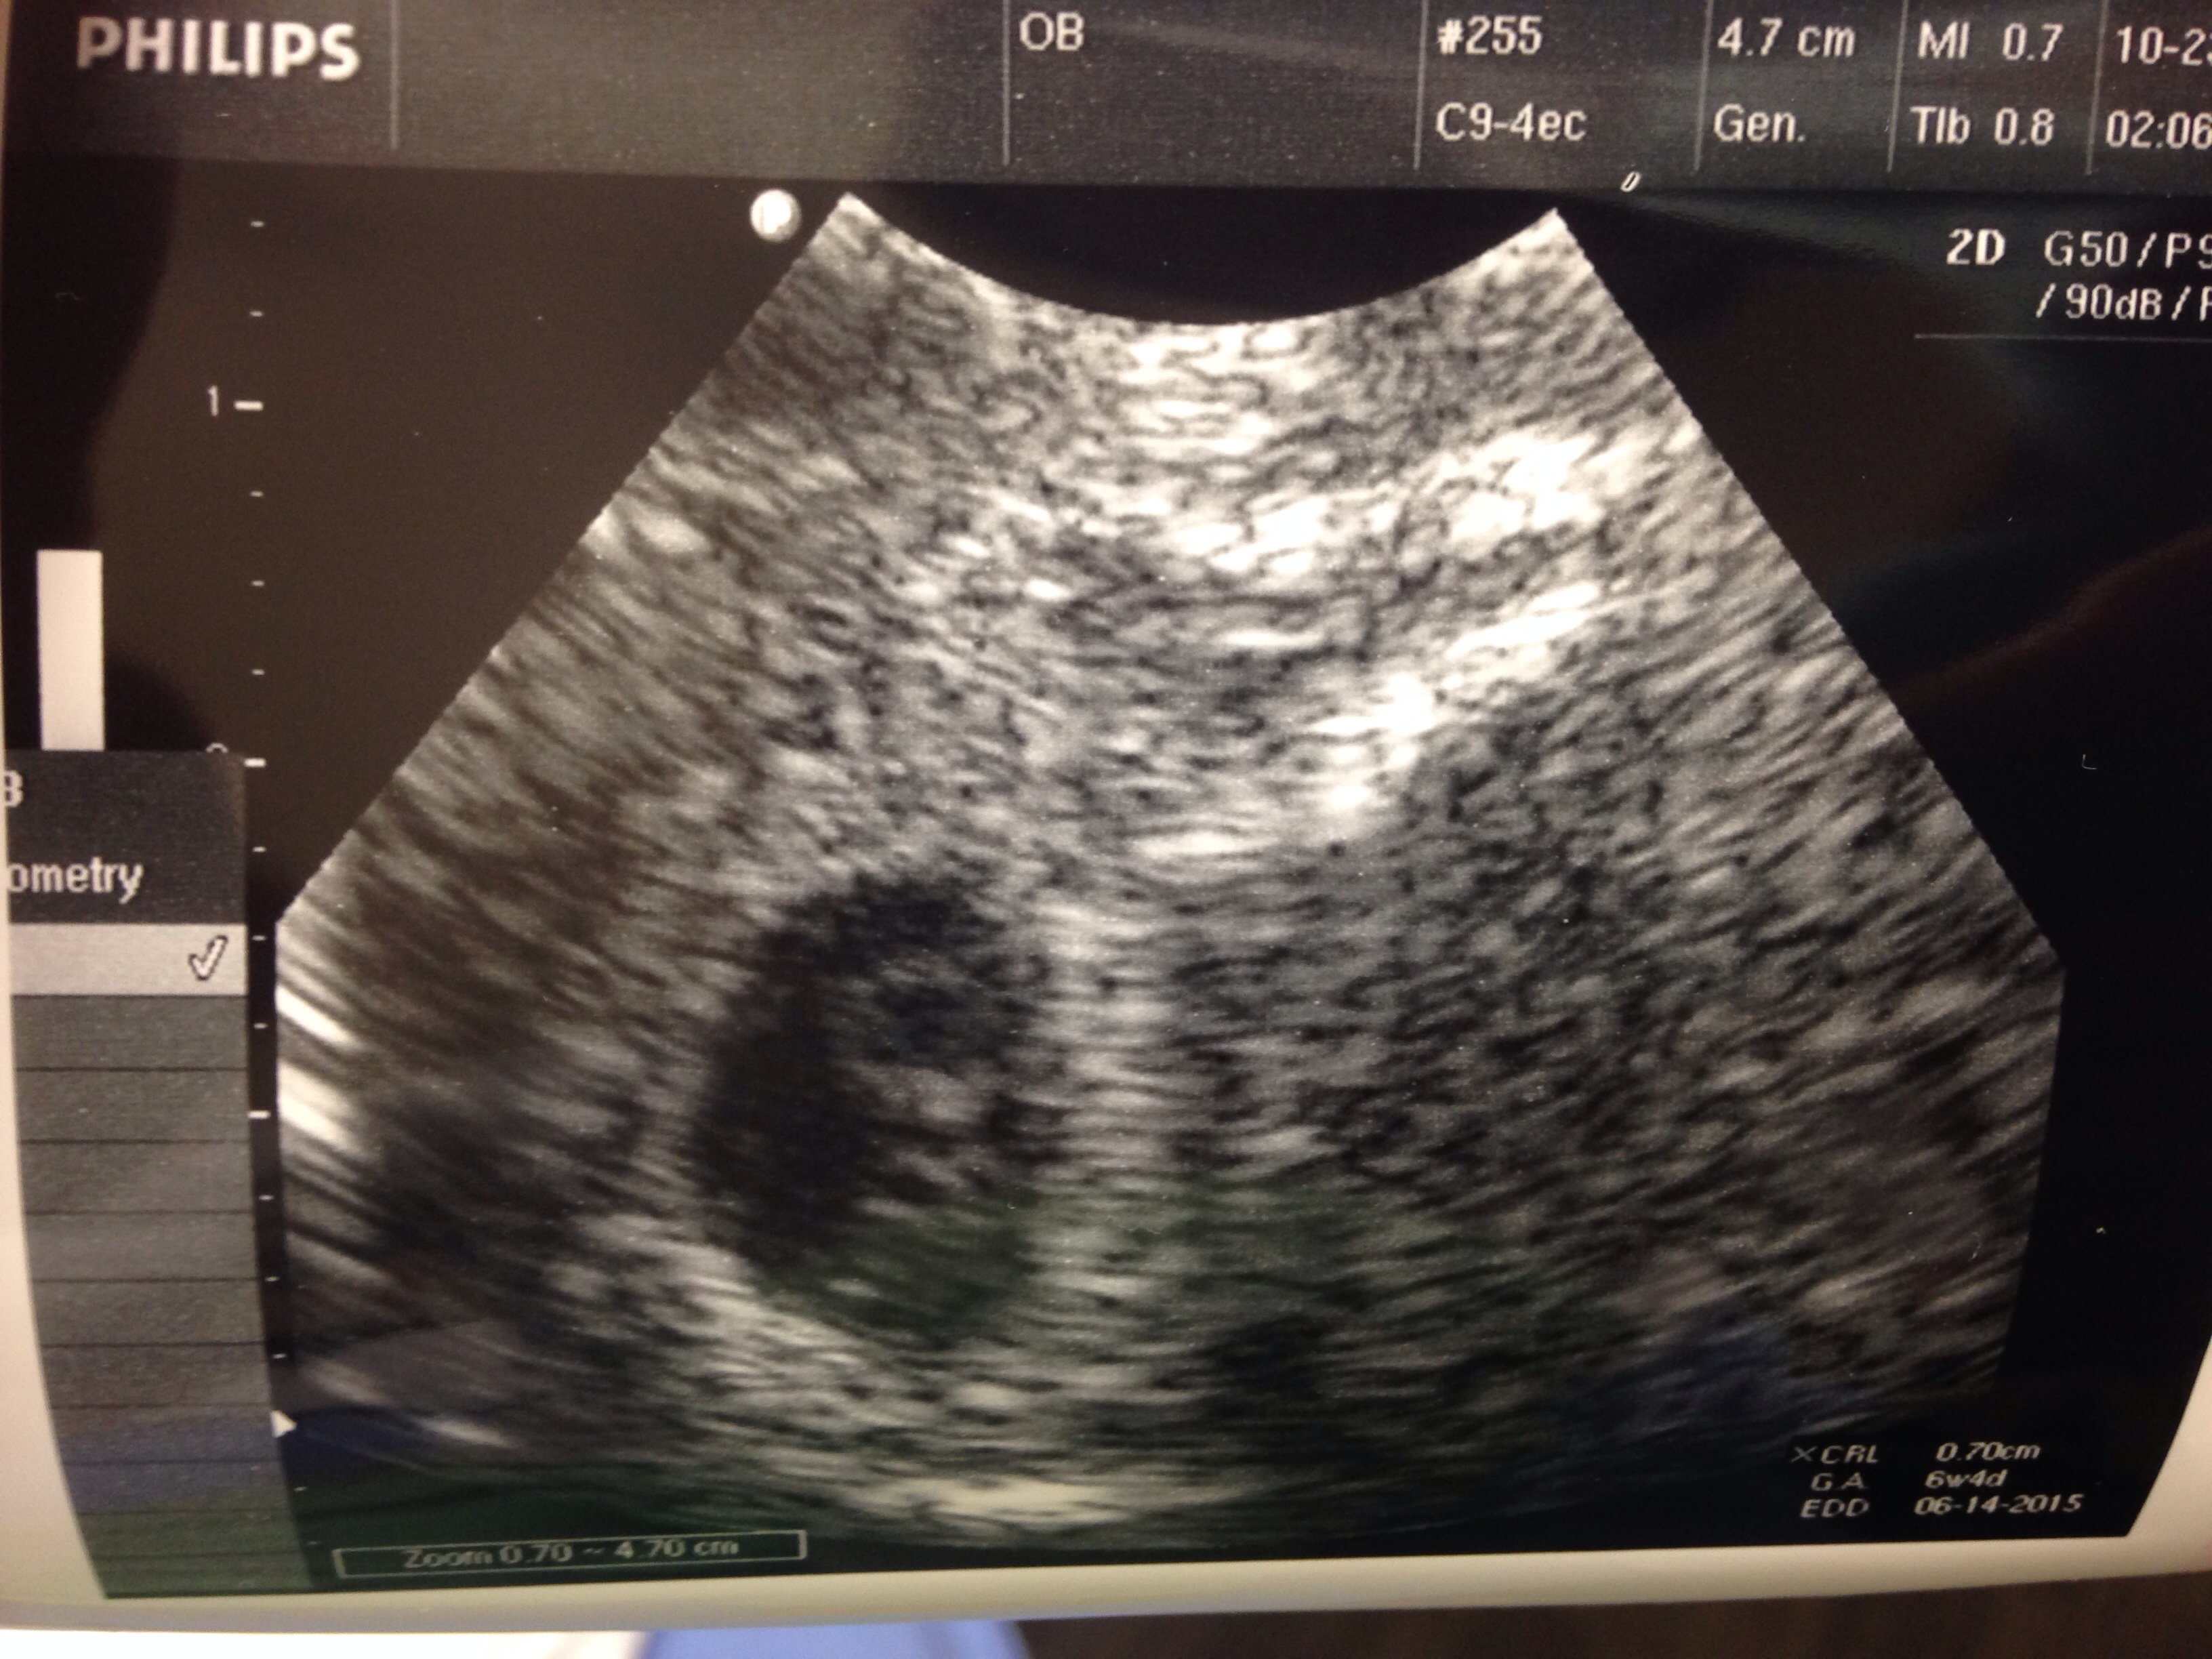

I went to the hospital today because of pink discharge and being rh negative. I had an ultrasound but the doctor who did it was doing her residency and didn't really explain. What do I see? Is the top part the sac? I'm confused. And do you see two bubbles at the bottom or am I seeing things? We only got one heartbeat, 130bpm